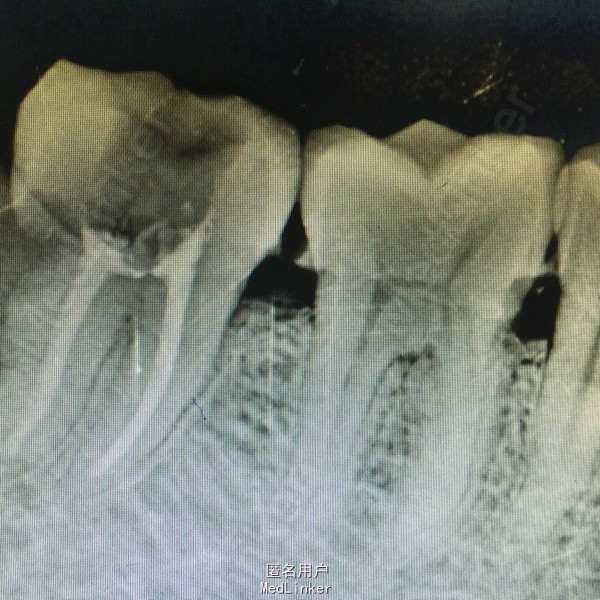

患者男性,40岁,右下后牙肿胀不适数日,近日疼痛加重张口受限,来院就诊。

查体:右面部肿胀,开口型正常,张口受限,48盲袋附着,溢脓,X线示48近中水平阻生,47远中邻面龋坏,龋坏深达牙髓腔。

诊断:48阻生齿,47牙髓炎 处理:48抗炎治疗,炎症控制后拔除48,数日后局麻下,47开髓揭髓顶,拔髓,冲洗进行根管疏通及测量,EDTA机用镍钛器械根管预备,次氯酸钠冲洗,进行热牙胶充填,Zoe暂封观察,建议嵌体修复。